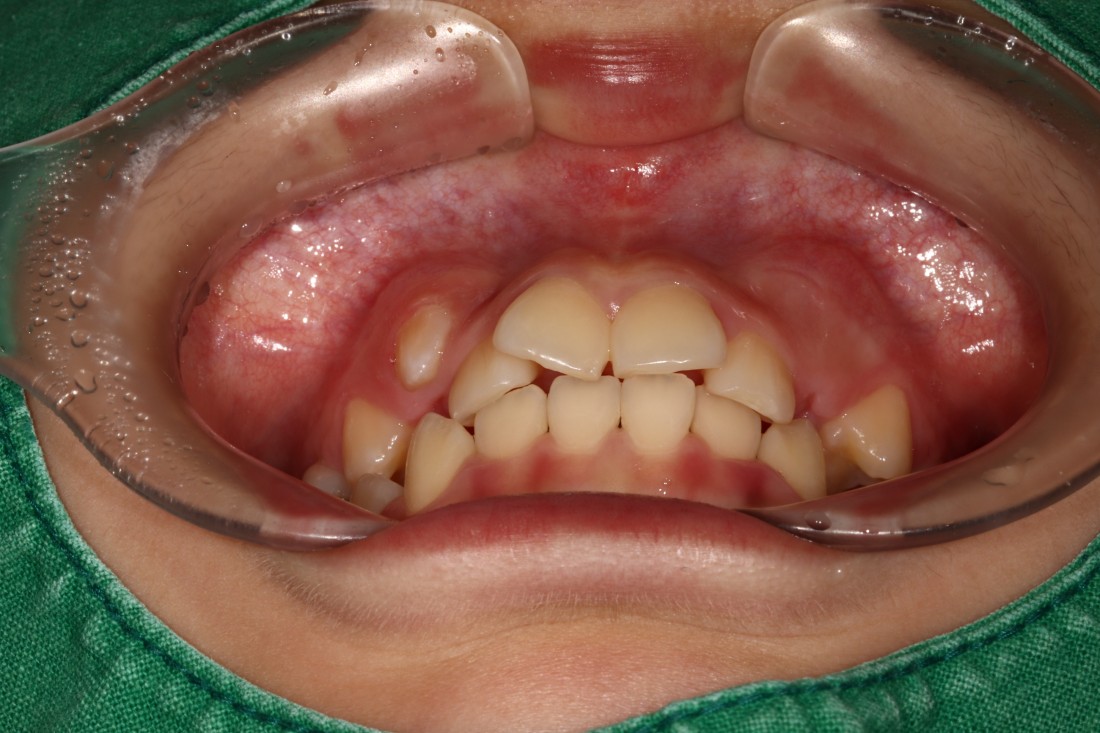

광주 덧니교정 치과에서는

덧니교정 시에

발치를 하는 경우도 있고,

비발치로 진행하는 경우도 있습니다.

치료계획은 모두 경험이 풍부한

교정전문의 대표원장님과

교정 전 정밀검사 결과를 토대로

오랜시간 세심한 상담 후에

결정하고 있습니다.

교정전문의가 봤을 때

발치가 꼭 필요한 경우가 있기 때문에

다양한 덧니교정 케이스와 비교하며

나만을 위한 치료계획을 세우고 있습니다.